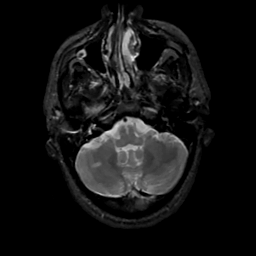

MR Study #15, June 9, 1991 -- Slice #10